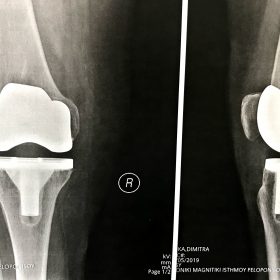

Παρόλα αυτά στην πλειονότητα των περιπτώσεων, με την πάροδο του χρόνου οι παραπάνω τρόποι αντιμετώπισης καθίστανται αναποτελεσματικοί. Η ένταση του πόνου και ο αντίκτυπος στην καθημερινότητα γίνονται αφόρητα.

Σε αυτό το σημείο η Αρθροπλαστική Γονάτου αποτελεί μονόδρομο.